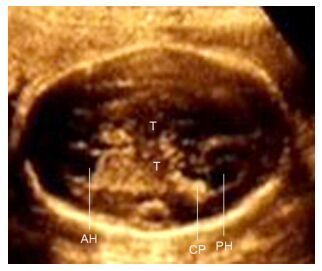

2 结果本例26周超声检查侧脑室前角宽约0.43 cm,后颅窝池宽约1.35 cm(如图 1)。于孕31+4 d复诊超声检查显示特征性的表现:侧脑室后角及前角室壁毛糙不规则,呈“锯齿状”,结节样的高回声锯齿状物凸向侧脑室壁内,同时合并有后颅窝池轻度增大宽约1.38 cm(如图 2)。本例足月分娩,女婴,产后2 d新生儿颅脑超声检查提示侧脑室壁回声毛糙(如图 3),与产前超声所见类似。新生儿头颅MRI检查考虑灰质异位,表现为双侧脑室外侧壁不光滑,呈“锯齿状”,T1WI呈稍高信号,T2WI呈低信号,与灰质信号近似(如图 4)。证实产前超声所见。产前未行染色体及基因检查。截至目前,本例1岁余,随访未见明显相关异常。

图 1 孕26周3 d超声检查结果 Figure 1 Ultrasound image of the fetus at 26 gestational week. The anterior horn of lateral ventricle (AH) was 0.43 cm, and the posterior cranial fossa was 1.35 cm. The wall of lateral ventricle was smooth, and the lesion was not obvious. T: Thalamus; CP: Choroid plexus; PH: Posterior horn of lateral ventricle. |